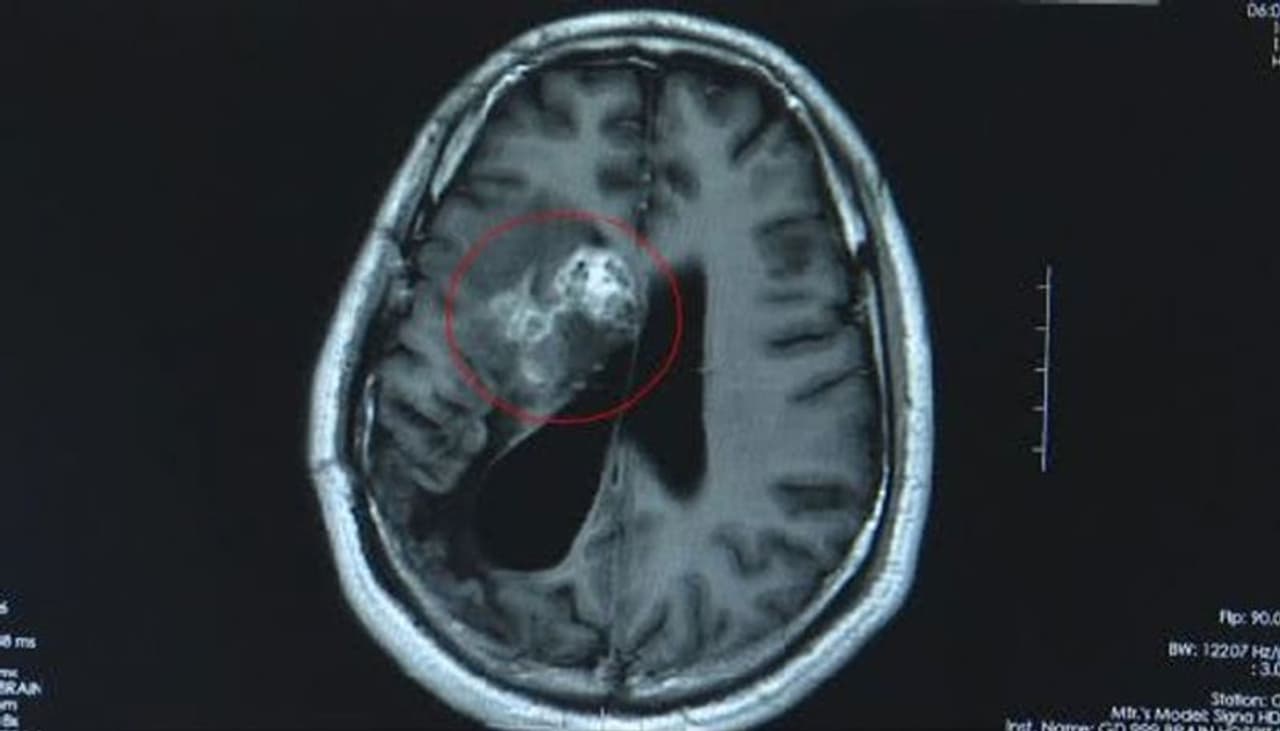

അയാളുടെ തലച്ചോറിനുള്ളില് നിന്ന് ജീവനുളള വലിയൊരു പുഴുവിനെയാണ് (Parasitic worm) ഡോക്ടര്മാര് കണ്ടെത്തിയത്. കഴിഞ്ഞ പത്ത് വര്ഷമായി അത് അയാളുടെ തലച്ചോറിനുളളിലുണ്ടായിരുന്നുവെന്നും ഡോക്ടര്മാര് പറയുന്നു. തലയുടെ ഇടത് ഭാഗത്തുണ്ടായ തരിപ്പ് ആയിരുന്നു ആദ്യത്തെ ലക്ഷണം. 2007ല് തുടങ്ങിയ ഈ ബുദ്ധുമുട്ട് മറ്റ് പല രോഗങ്ങളുടെയും ലക്ഷണമാകാമെന്നാണ് പരിശോധിച്ച ഡോക്ടര്മാര് ആദ്യം പറഞ്ഞത്.

എന്നാല് 2018ഓടെയാണ് തലച്ചോറിനുളളിലെ പുഴുവിനെ ഡോക്ടര്മാര് കണ്ടെത്തിയത്. 12 സെന്റിമീറ്റര് നാളത്തിലുള്ള പുഴുവായിരുന്നു വാങിന്റെ തലയ്ക്കുള്ളില് ഉണ്ടായിരുന്നത്. മനുഷ്യ ശരീരത്തിനുള്ളില് ഇത്രയും വലിയ പുഴു ജീവിക്കുക അസ്വഭാവികമായ കാര്യമാണെന്ന് ഡോക്ടര്മാര് പറയുന്നു. രണ്ട് മണിക്കൂര് നീണ്ട ശസ്ത്രക്രിയയിലൂടെയാണ് പുഴുവിനെ പുറത്തെടുത്തത്.